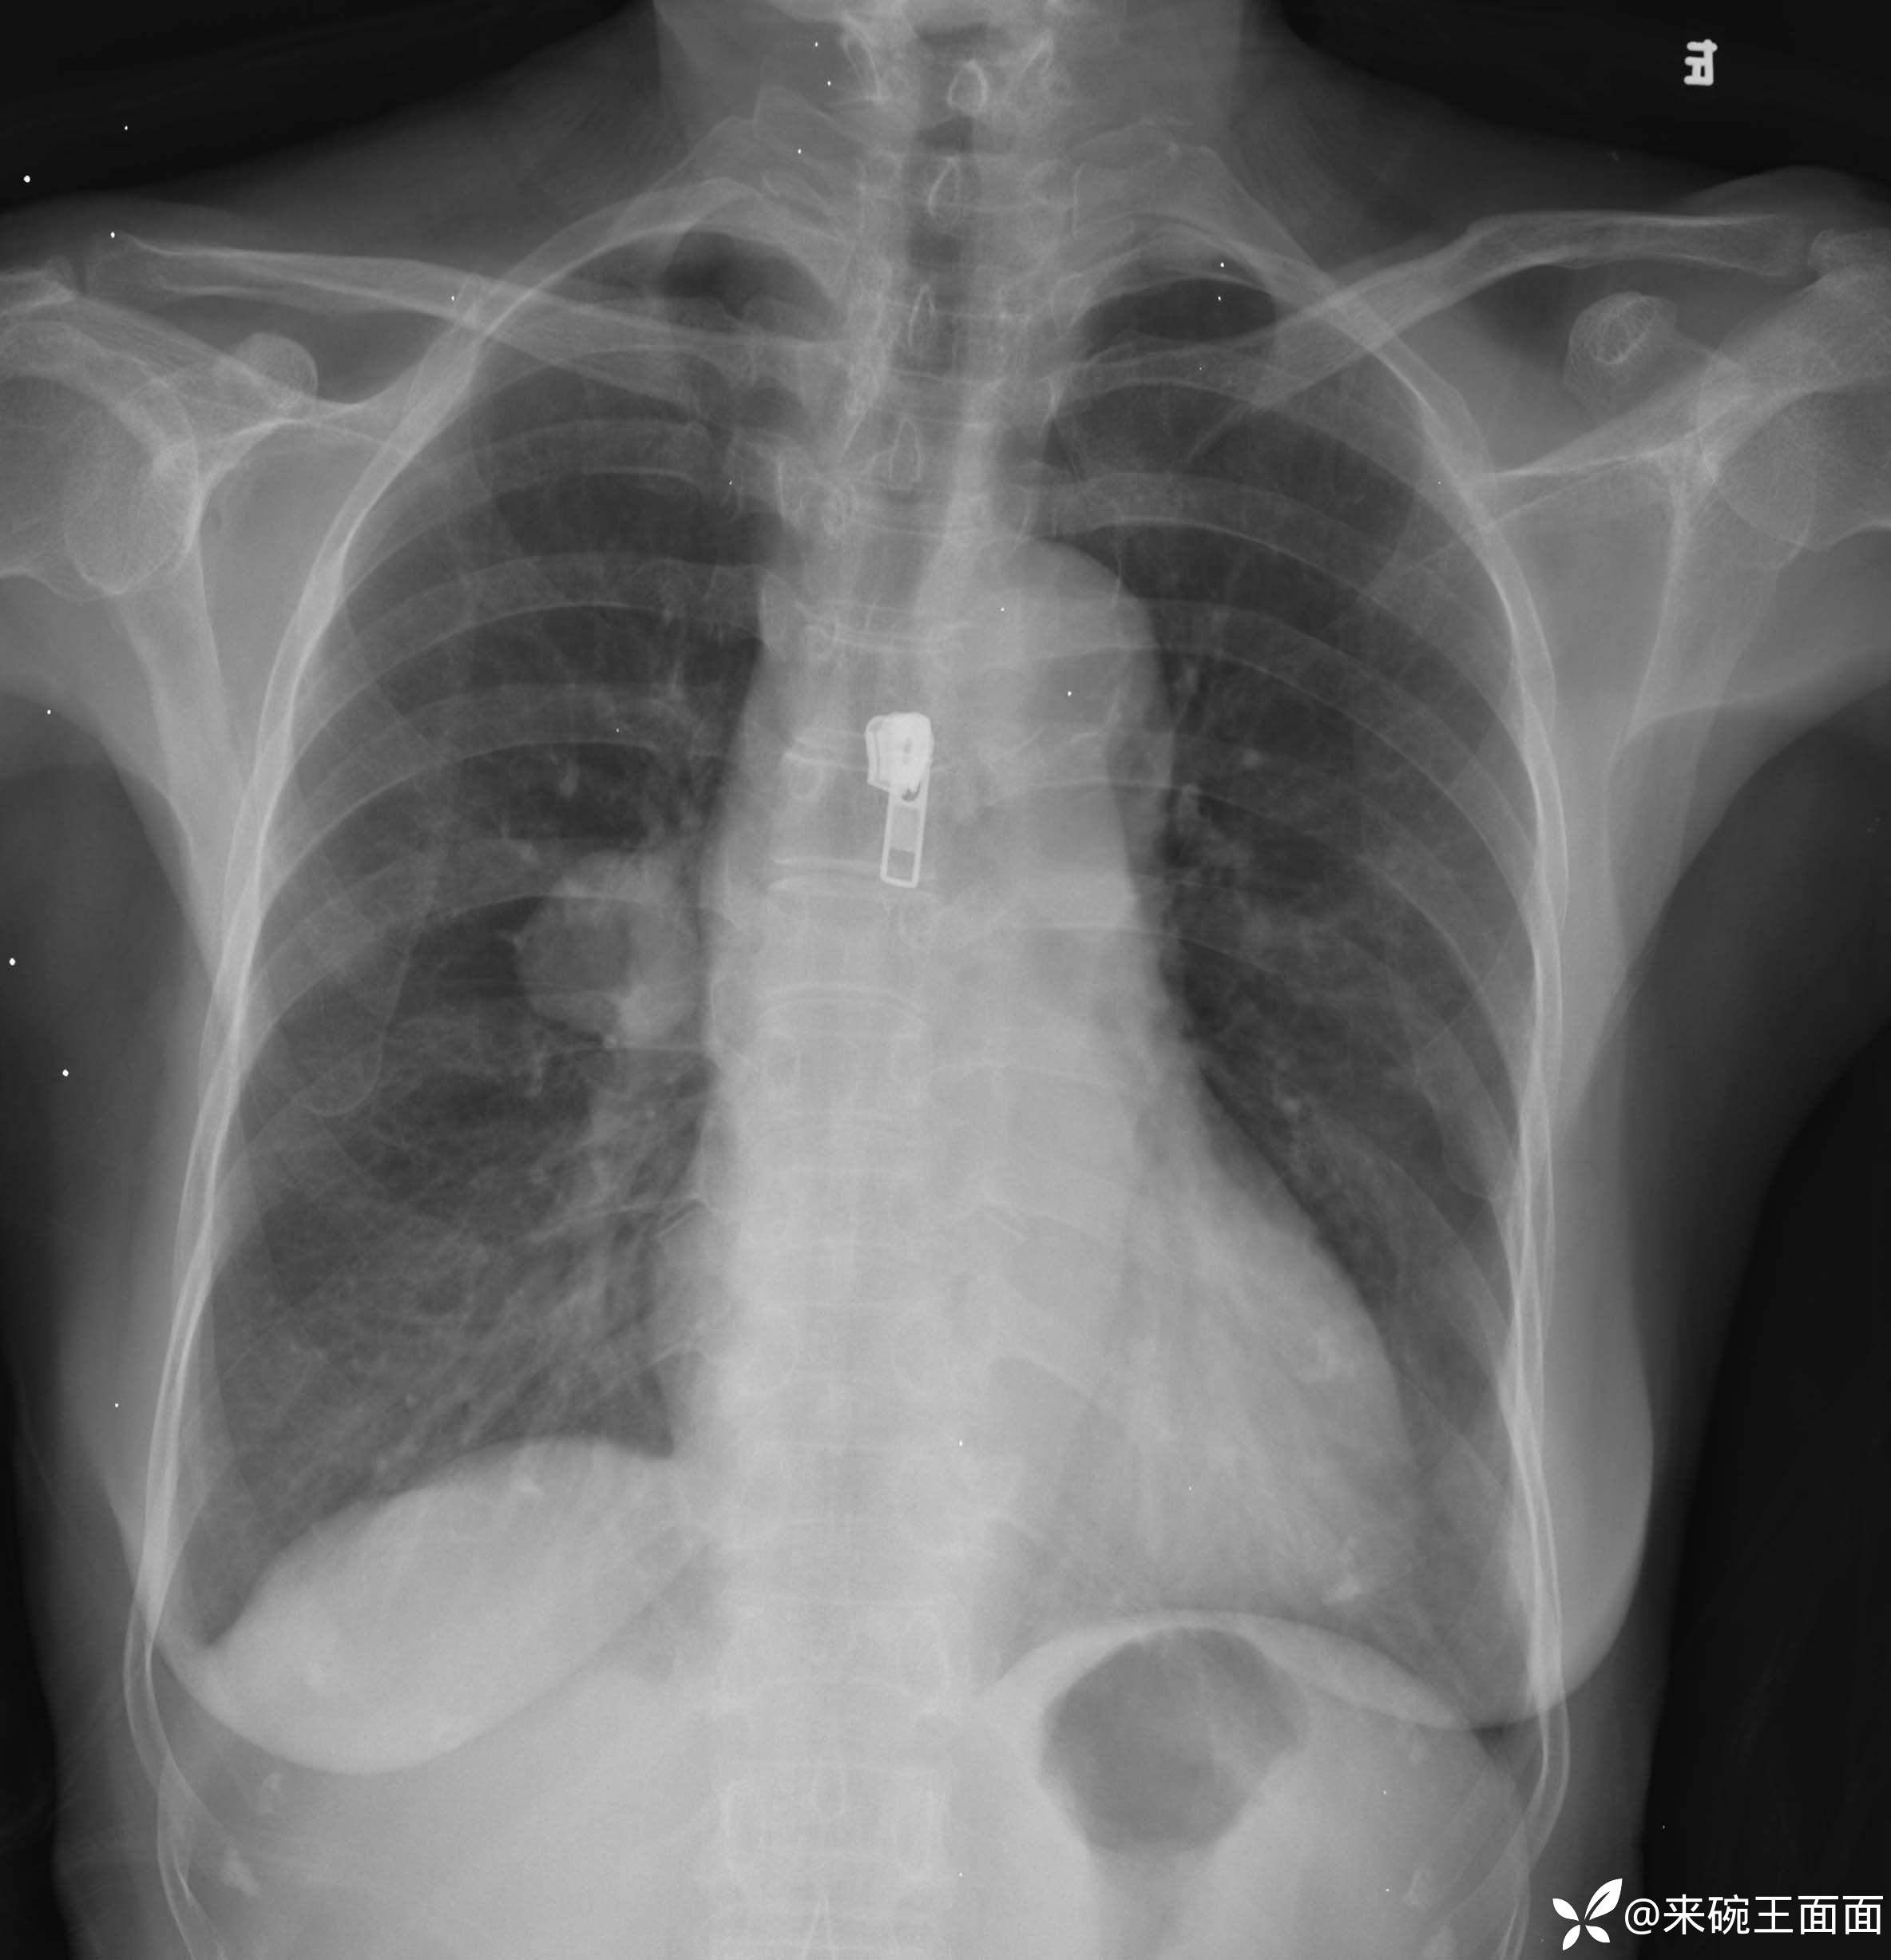

详情:右肺门类圆形肿块,边缘光整,增强扫描肺门侧可见一血管与肿块相连,且该病灶边界清晰,其密度均匀。对周围结构无明显影响。